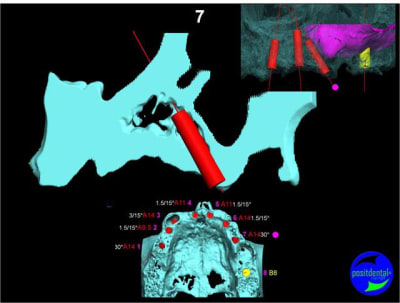

Extraction, pose d’implants Ankylos, pose des piliers Standard définitifs, mise en charge immédiate bi-maxillaire en une chirurgie.

Maxillaire supérieur – extraction 13, 26, 7 implants en MCI, 1 implant en MCR pose summeurs, densification par ostéotme, comblement osseux, bridge provisoire sans fausse gencive avec renfort métallique.

Maxillaire inferieur – extraction 35, 34, 44, 45, 6 implants MCI, comblement osseux, bridge provisoire sans fausse gencive avec renfort métallique.

3D

uniquement le scan pré-op

en attendant la pano voici les coupes de la S.I.A.O.